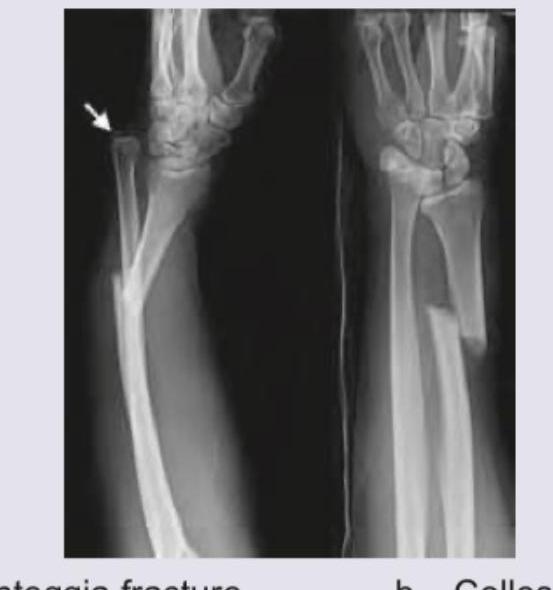

A child presented with pain in the forearm following a trauma. An AP and lateral X-ray of the forearm reveal the findings as shown. What is the most likely diagnosis? (Recent NEET Pattern 2016-17)

Explanation: ***Monteggia fracture*** - This classic injury pattern shows **fracture of the ulnar shaft** with **dislocation of the radial head**, more commonly seen in children due to their ligamentous laxity and softer bones. - Diagnosis is confirmed using the **radiocapitellar line test** - a line drawn through the center of the radial head should pass through the capitellum on all X-ray views; disruption indicates radial head dislocation. *Colles fracture* - A Colles fracture involves a **fracture of the distal radius** with **dorsal displacement** of the distal fragment, typically occurring from a fall on an outstretched hand in elderly patients. - The X-ray findings clearly show an **ulnar shaft fracture** with **radial head dislocation**, not a distal radial fracture pattern. *Smith's fracture* - A Smith's fracture is a **distal radius fracture** with **volar (palmar) displacement** of the distal fragment, sometimes called a "reverse Colles fracture." - This diagnosis is incorrect because the image demonstrates a **midshaft ulnar fracture** with **proximal radioulnar joint disruption**, not distal radial pathology. *Galeazzi's fracture* - A Galeazzi fracture involves a **fracture of the radius** (usually distal third) combined with **dislocation of the distal radioulnar joint (DRUJ)**. - This pattern is distinct from the current case, which shows **ulnar fracture** with **radial head dislocation** at the **proximal radioulnar joint**, making it a Monteggia rather than Galeazzi injury.